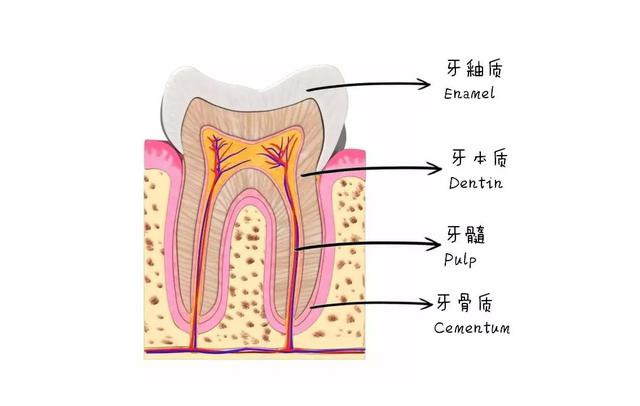

牙齿根管结构分布图

jpg,490x600,214880b